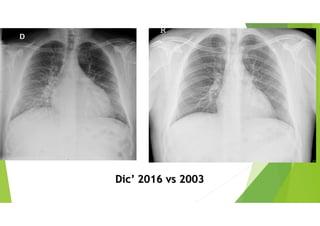

Dic’ 2016 vs 2003

Edema en cisura mayor. Sin RHY, sin edemas MMII, sin RA en AR....

Pero con disnea progresiva, DPN y ortopnea... Y Fx renal alterada...